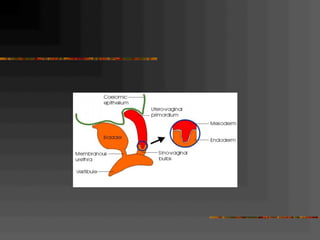

Paramesonephric

Adult Equivalents of Embryonic Structures

FemaleEmbryonic Structure

ovaryIndifferent gonad

ovarian folliclesCortex

rete ovariiMedulla

ovarian and round ligament of uterusGubernaculum

epoophoron, paroophoronMesonephric tubules

appendix vesiculosa, duct of epoophoron, duct of Gartner,

ureter, pelvis, calices and collecting tubules

Mesonephric Duct

hydatid of Morgagni, uterine tube, uterusParamesonephric Duct

urinary bladder, urethra, vagina,

urethral, paraurethral and greater vestibular glands

Urogenital Sinus

hymenSinus tubercle

clitorisPhallus

labia minoraUrogenital folds

labia majoraLabioscrotal swellings

Adult Equivalents ofEmbryonic Structures FemaleEmbryonic Structure ovaryIndifferent gonad ovarian folliclesCortex rete ovariiMedulla ovarian and round ligament of uterusGubernaculum epoophoron, paroophoronMesonephric tubules appendix vesiculosa, duct of epoophoron, duct of Gartner, ureter, pelvis, calices and collecting tubules Mesonephric Duct hydatid of Morgagni, uterine tube, uterusParamesonephric Duct urinary bladder, urethra, vagina, urethral, paraurethral and greater vestibular glands Urogenital Sinus hymenSinus tubercle clitorisPhallus labia minoraUrogenital folds labia majoraLabioscrotal swellings